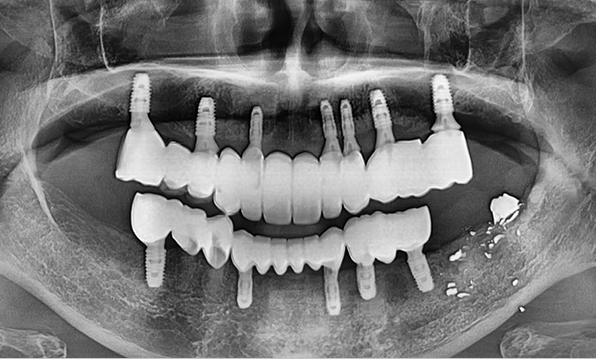

전체 임플란트는 위턱과 아래턱의 교합, 잇몸뼈의 상태 및

얼굴 변화 등 모든 것을 고려해 식립해야 합니다.

서울더자연치과는 3D 디지털 기술의 정밀 진단을 바탕으로

수술 계획을 세워 수술을 집도합니다.

치료기간 : 2021.04.12~2021.09.15